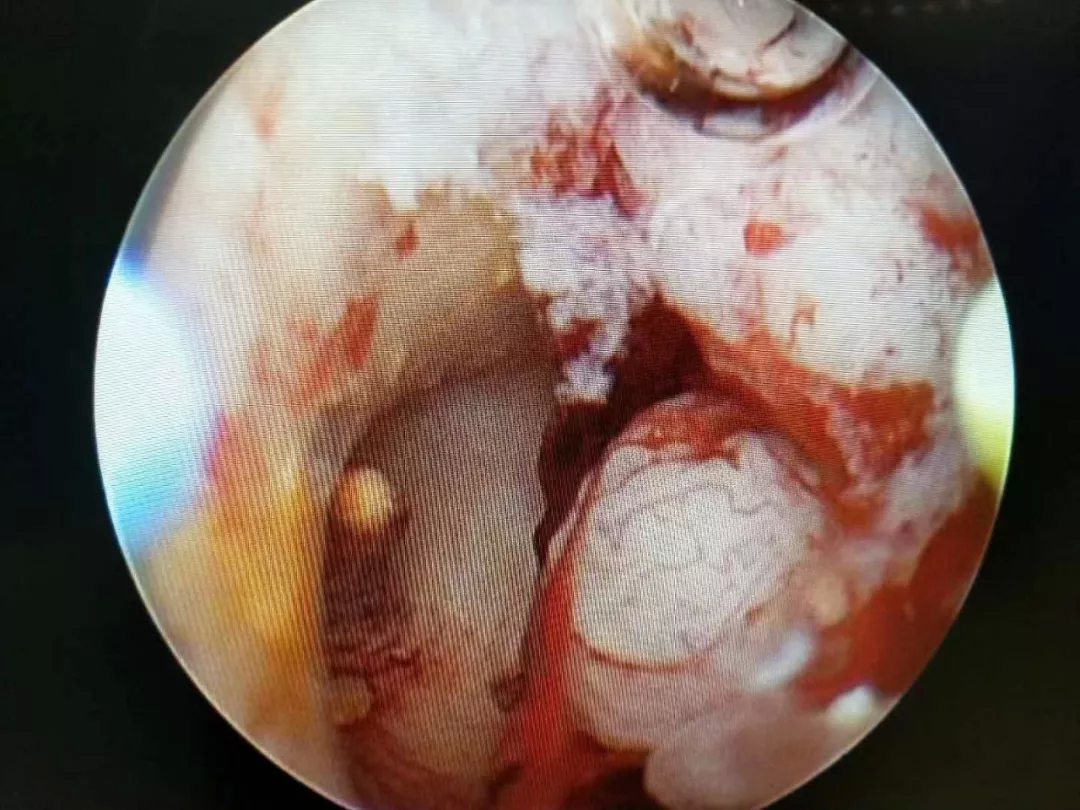

宫腔镜下的子宫内膜息肉

子宫肌瘤

切除子宫内膜息肉,解决不孕难题

张女士结婚两年多一直未怀孕,经人介绍来到青岛西海岸新区中医医院妇科就诊。张女士的B超检查结果无任何异常,遂计划行IVF-ET术(俗称“试管婴儿”)。术前,褚静萍主任为其进行了宫腔镜常规检查,发现双侧输卵管开口处多发息肉,呈簇状,分别约1.5X1.5cm子宫内膜息肉并及时进行了切除。张女士术后3月,还没有去做试管婴儿的张女士意外的发现自己怀孕了,向褚主任发来微信表示感谢。